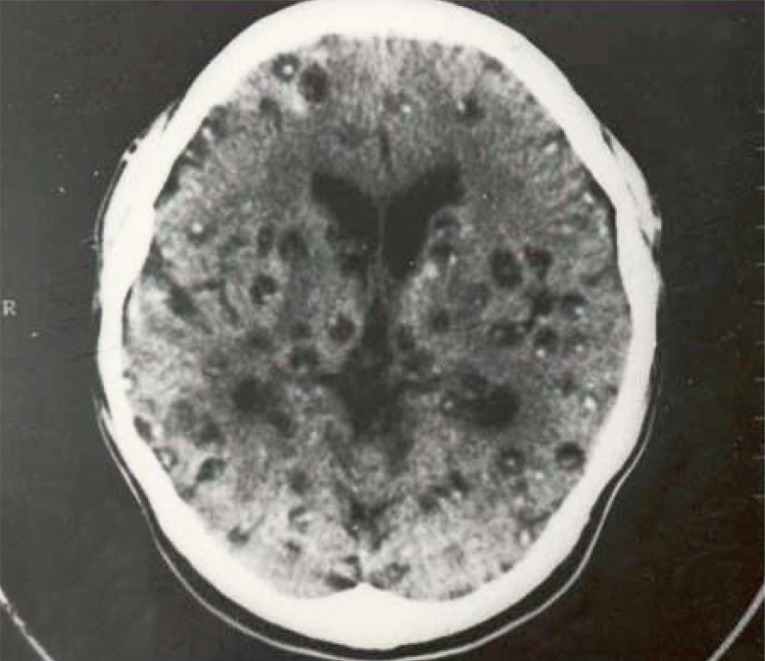

The major symptoms of human cysticercosis included headache 65.9-90.4%, epilepsy 56.4-67.5%, quickened muscle 35.3-48.9%, losing memories 42.4-46.9%, sleeplessness 40.3-46.4%, hearing disorders 36.4-42.4%, nausea/vomiting 39.2-40.8%, paralysis 28.4-30.8%, feeling disorder 18.2-20.1%, biopsy positives in subcutaneous tissues 92.2-95.4%, increased eosinophils 83.4-84.5%, positive ELISA with Taenia antigen 85.1-86.6%, and positive MRI/CT scan with live cysts in the brain 90.1-92.2% [8,10]. Subcutaneous cysts were found in back-chest 36.6%, hands 28.7%, head-face-neck 18.2%, and legs 17.4%. The highest number of subcutaneous nodules was 300 cysts in a patient (Fig. 3) [13]. Regarding the number of cysticercus cellulosae cysts in the brain, patients with <20 cysts were 53.3%, and those with ≥20 cysts was 46.7%. The highest number of cysticerci in the brain was 300 (Fig. 4) [13].

In 100 neurocysticercosis patients, the form of cysts included vesicular nodule 83%; colloidal vesicle 100%; granular nodule 81%, calcified nodule 96%, mixture of 4 forms 78%; and colloidal vesicle only 11%. There were 50% patients that showed spread-stimulated waves in electro-encephalography, 27% patients that showed local stimulated waves, and 9% patients with unusual electro-encephalography with theta waves [8].